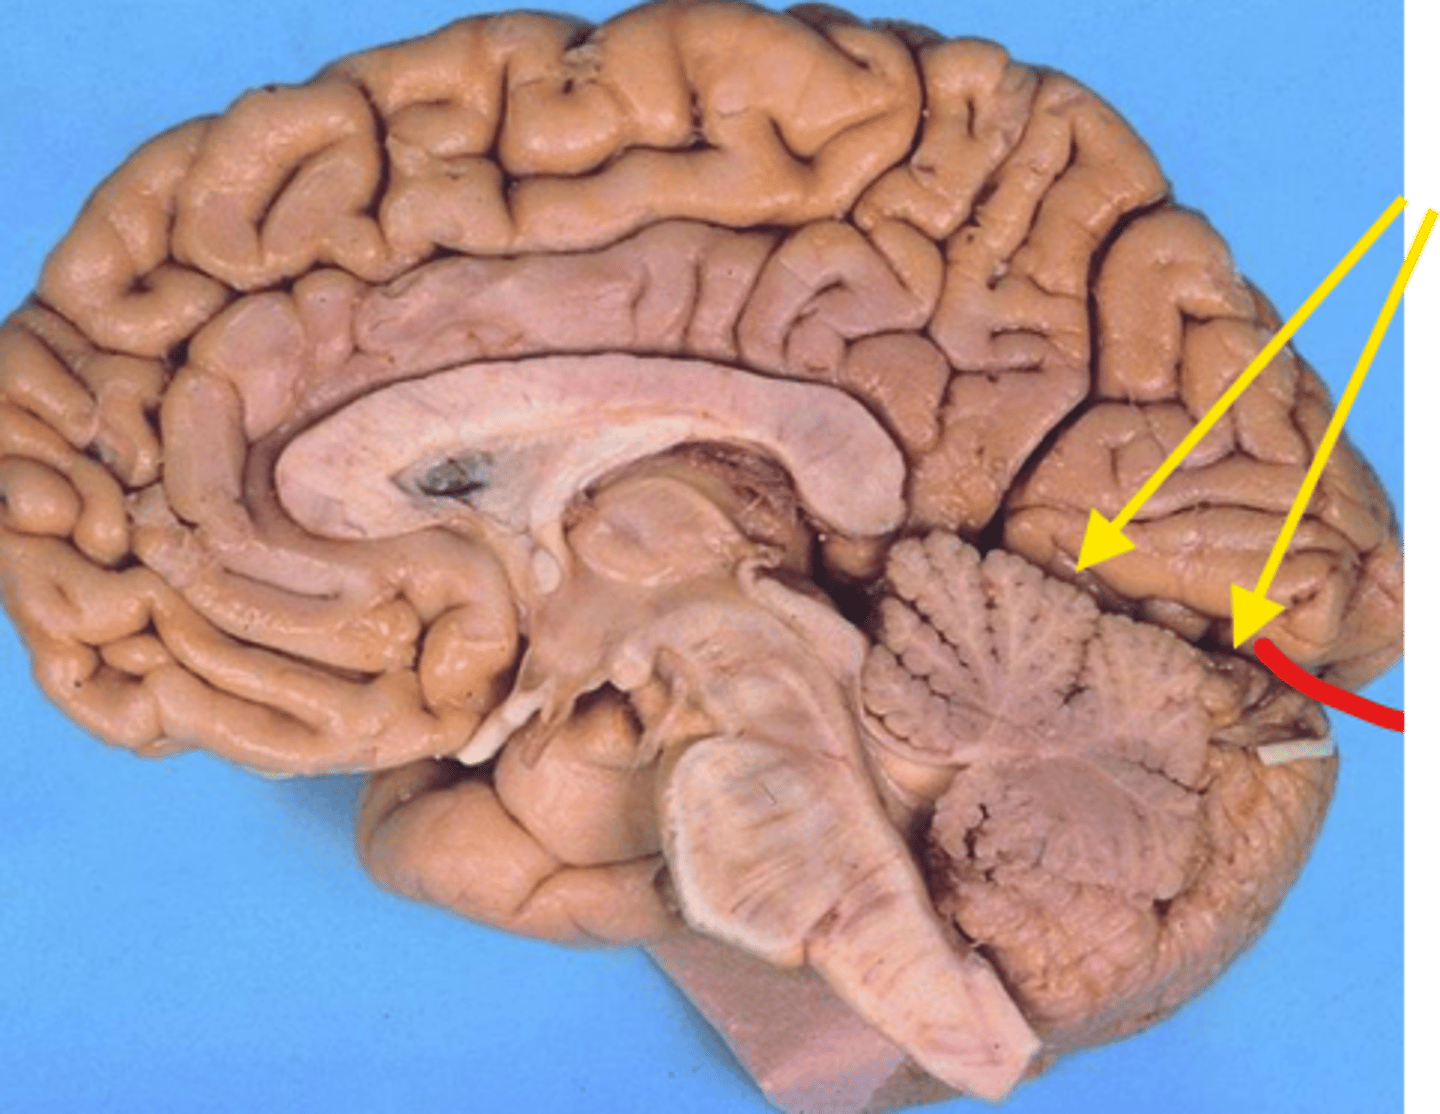

What space is the yellow arrow pointing to?

what space is the yellow arrows pointing to?